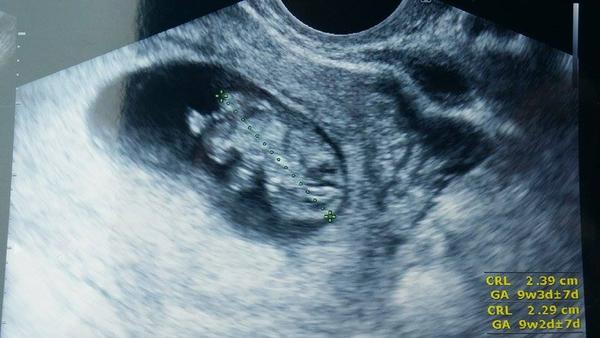

Ahoj holky tak se hlásím s nejlepší zprávou.Včera konečně nadešel den D a my jeli s manželem na kliniku na UZT na potvrzení srdíčka.To že jsem těhotná už mě potvrdil můj gyn. před 14 i s fotečkou dutinky na UZT, ale to co nás čekalo na klinice bylo fakt překvapení.Místo jednoho srdíčka nám bily srdíčka dvě a jako o závod.Takže čekáme dvojčátka.Přikládám foto ze včerejška.